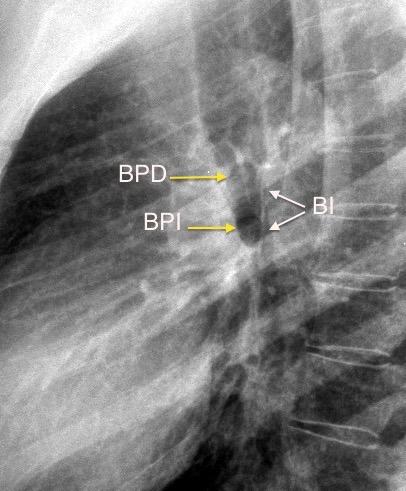

Patología

¡Visualización buena!

Sospecha de ganglios aumentados, en el hilio derecho . Proto AV.1979

Sarcoidosis

Whitten CR. A Diagnostic Approach to Mediastinal Abnormalities. Radiographics 2007 / Marano R et al. Cardiac Silhouette findings And mediastinal lines and stripes. Chest. 2011